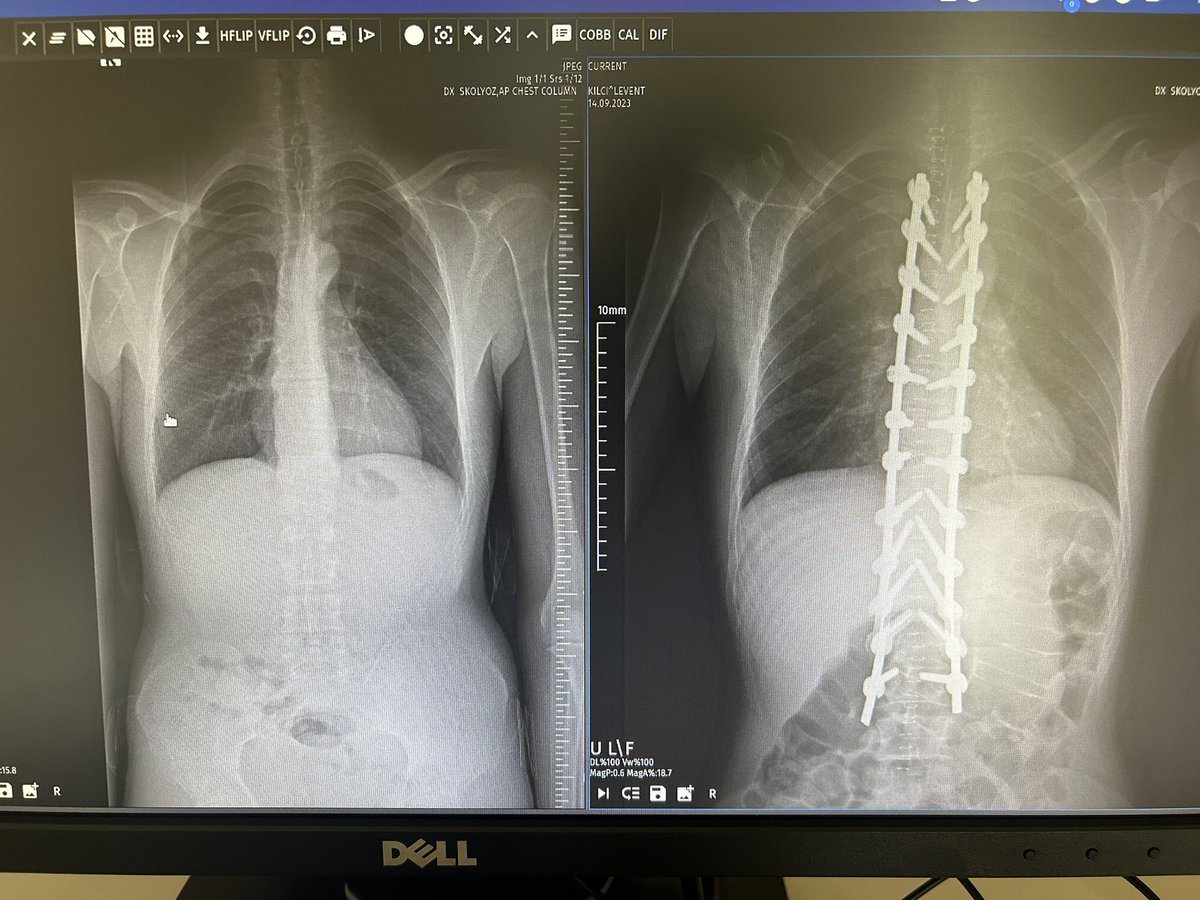

10 y o male, congenital kyphosis case. treatment with kyphectomy and double fibula allograft. #spinesurgery #spine